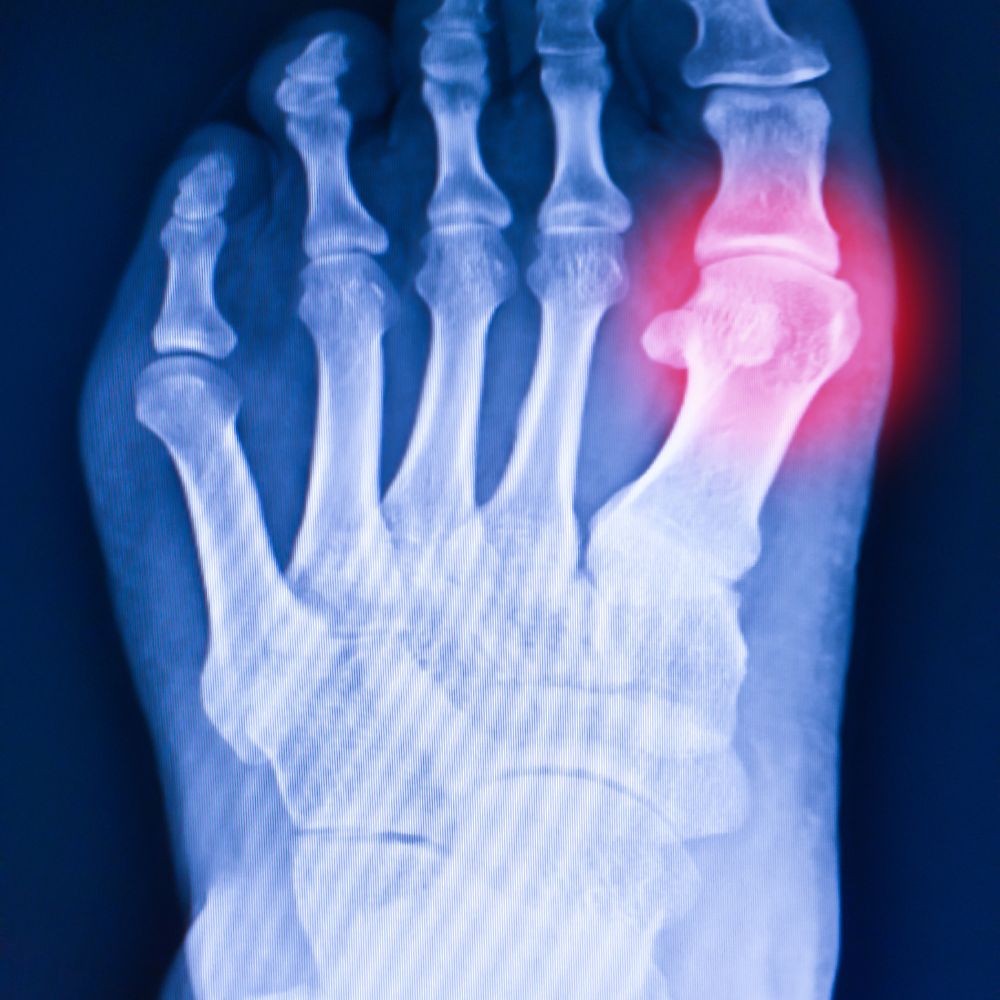

- 통풍 결절: 요산 결정이 피부 아래에 덩어리(결절)로 쌓일 수 있습니다. 주로 팔꿈치, 귀, 손가락, 발가락, 발목 등에서 관찰됩니다.

- 영상 검사: X-ray, 초음파, CT 등으로 관절 및 결절 상태 확인